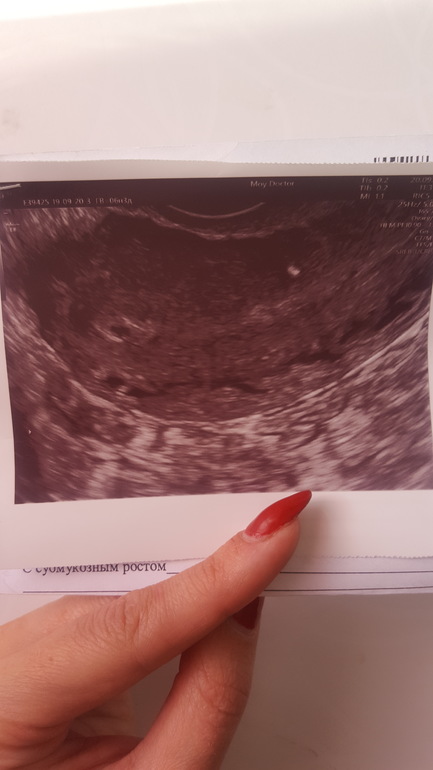

Девочки, добрый день. У кого было так же? Чего ждать? Ситуация у меня такая. Мы с мужем как и все, планируем детей , поэтому тесты мы покупаем постоянно. Последняя менструация была 6.08.19 , но месячные пришли раньше на 5-6 дней, цикл у меня 27-28 дней. Вообще, я их ждала числа 11-12. Отталкиваясь от месячных 6.08 , в сентябре я ждала их приход 2 числа , ну максимум 6. Они не пришли, делаю тест - слабоположительный,цифровой показал слабый плюсик, недельный "не беременна", я подожлала и 10.09 уже 2-3 недели , но все так же слабоположительные полосочки. И вдруг начались коричневастые не обильные выделения , такое бывает , когда застудишься еще 🙊 я испугалась, что это или выкидыш, или тест ошибся и это пошли эти дни все таки с задержкой, т.к выделения были дней 6-7 и начались примерно тогда , когда я ждала месячные.. записалась на УЗИ , врач смотрела меня очень долго , не могла найти то самое заветное зернышко, а то что нашла , указала как "подозрение на беременность малого срока или на неразвивающуюся(?), D=2 мм возможно плодородное яйцо, может быть и ложное плодородное яйцо", ну как так... По фото УЗИ она сказала, сто возможно это не плодородное яйцо вовсе , а та часть матки , к которой оно цепляется и эта часть вот так вот выглядит. И вообще, овуляция произошла в правом яичнике и тест положительный, то это может быть внематочная... ну что за диагноз такой ((( я пошла купила тест - уже явные 2 полоски и срок 2-3 недели (может быть, тест в прошлый раз ошибся, ведь сначала она написал "не беременна", а потом сразу же через неделю 2-3 недели"). Это было 20 сентября. На след.прием сказали записаться лучше 10-20 октября.. вот жду.. И на этих выходных опять небольшие выделения начались, но на много меньше , (только когда схожу в туалет и не всегда), чем в тот раз, но я очень сильно нервничала, так как наши родители попали в аварию и я хорошо стрессанула из-за этого.. совсем запуталась в сроках , в показаниях, голова кругом... У кого было так же? Чего ждать ? Фото прикрепляю, яичники: правый 3.5*1.8*2.3, V = 5.8, с желтым телом 1.8 мм, фолликулы D 3-5 мм, левый: 2.9*1.3*1.2, V = 2.4 мм, фолликулы D 2.0-6.0 .